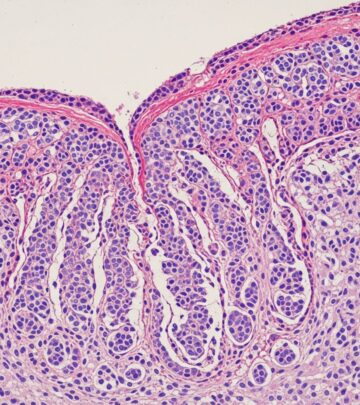

Tissue is sectioned, frozen, stained, and mapped. The surgeon microscopically checks 100% of edges and deep margins for cancer cells, noting exact locations if positive.